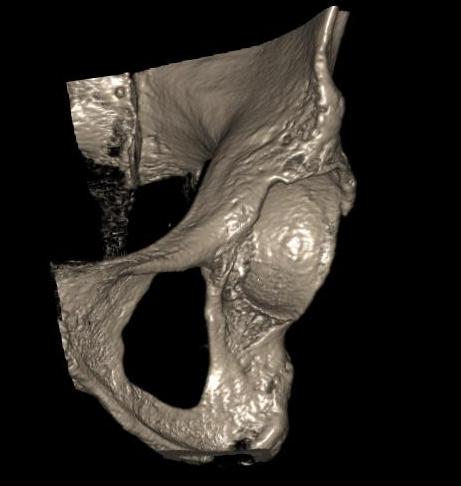

CT

Configuration

1-2 mm sections

CT reconstruction

- remove head to view acetabulum

- beware volume averaging

- used to guide surgery